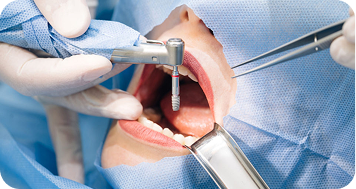

CBCT e diagnóstico endodôntico

CBCT transforma o diagnóstico endodôntico com precisão 3D e altera condutas. Veja como essa tecnologia impacta a prática clínica. Leia mais.